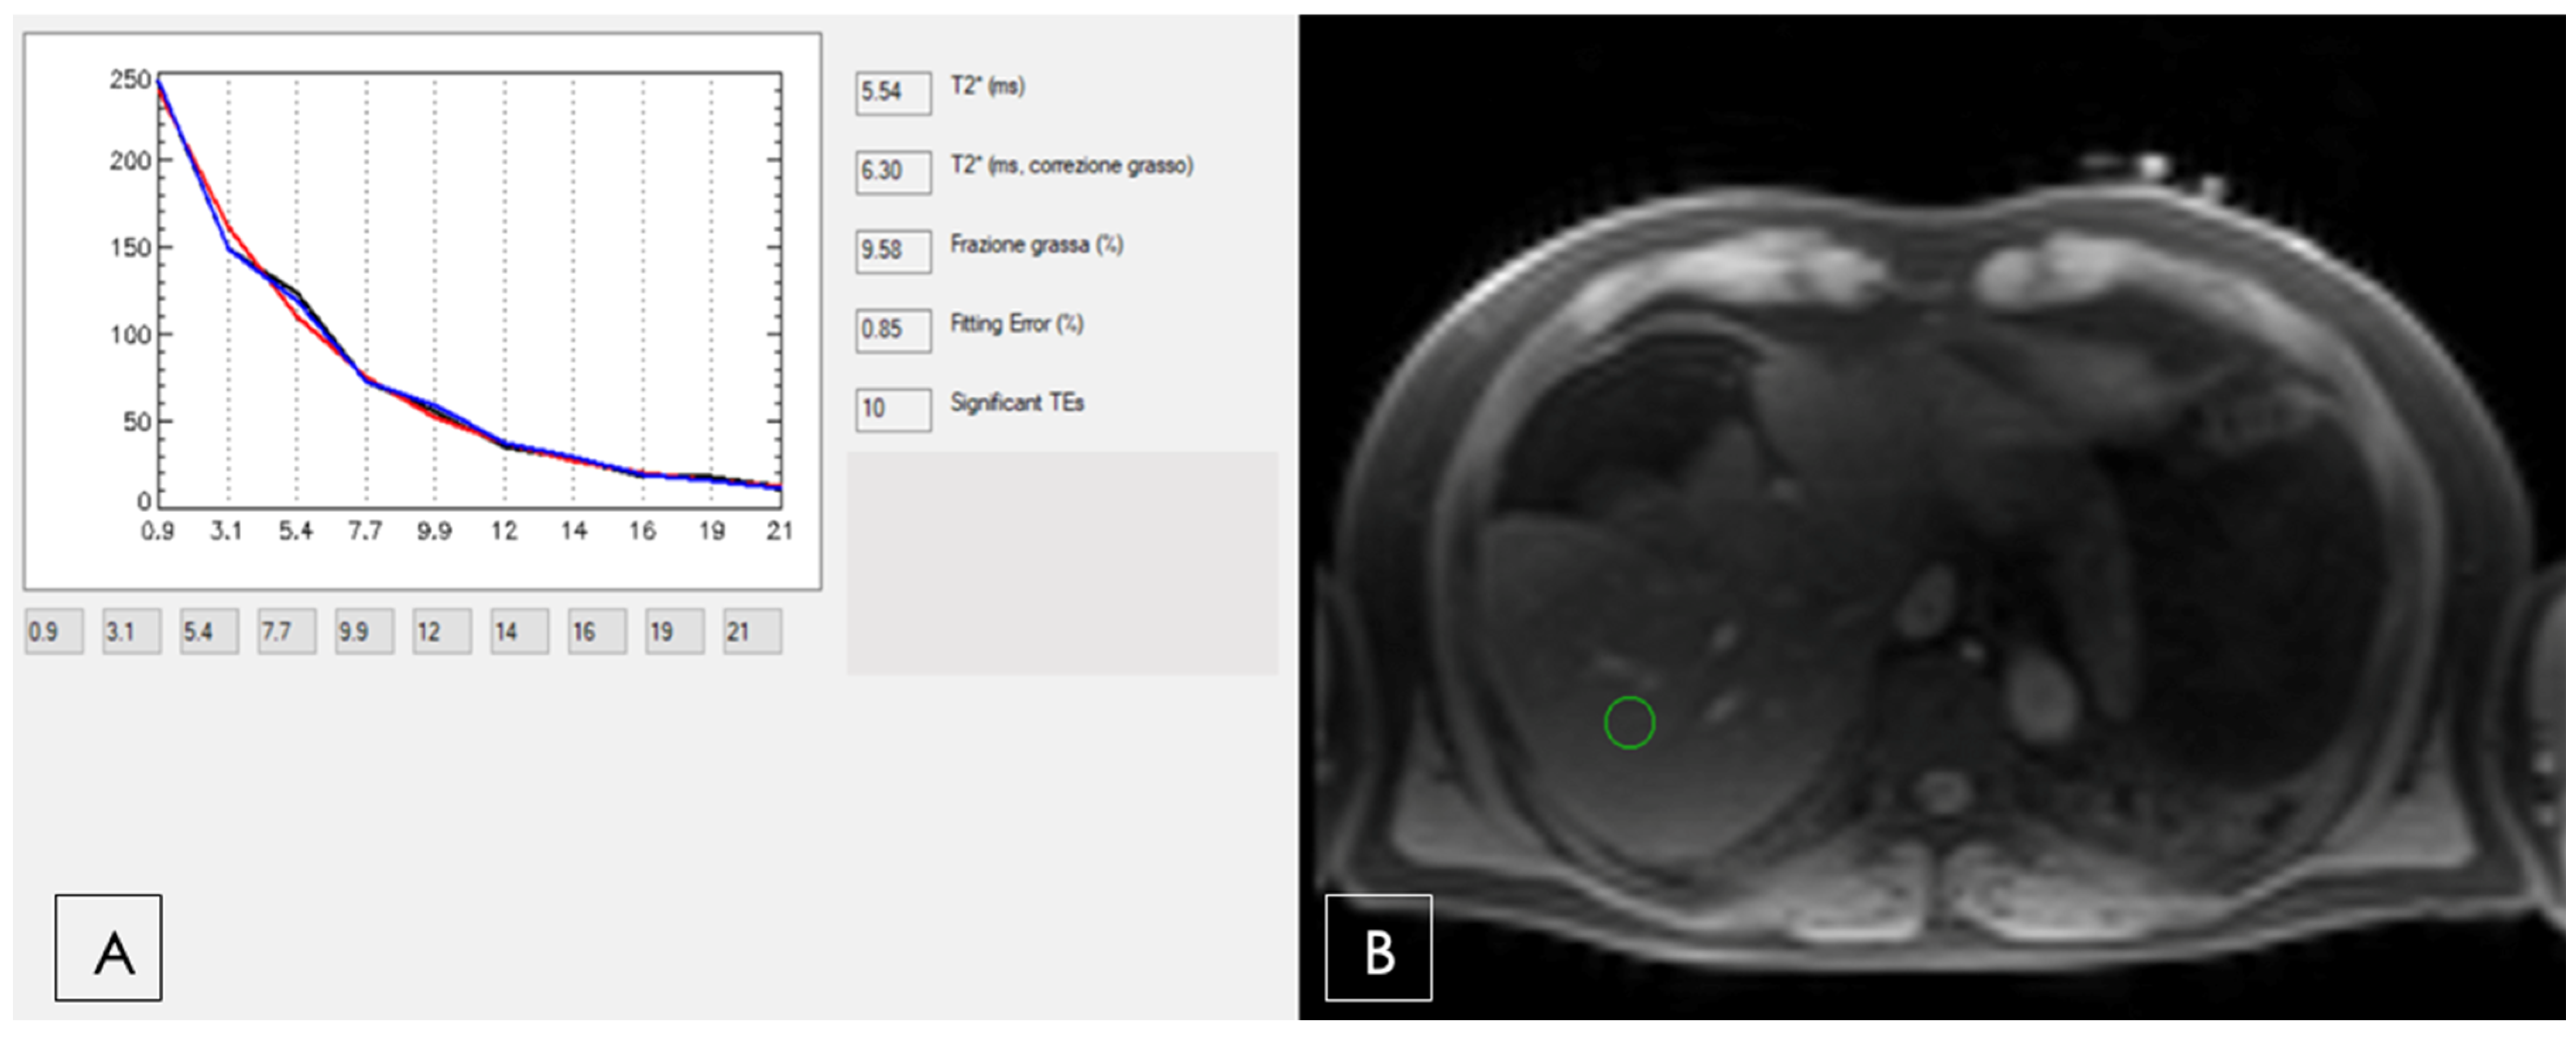

- Positano, V.; Salani, B.; Pepe, A.; Santarelli, M.F.; De Marchi, D.; Ramazzotti, A.; Favilli, B.; Cracolici, E.; Midiri, M.; Cianciulli, P.; et al. Improved T2* assessment in liver iron overload by magnetic resonance imaging. Magn. Reson. Imaging 2009, 27, 188–197. [Google Scholar] [CrossRef]

- Meloni, A.; Positano, V.; Keilberg, P.; De Marchi, D.; Pepe, P.; Zuccarelli, A.; Campisi, S.; Romeo, M.A.; Casini, T.; Bitti, P.P.; et al. Feasibility, reproducibility, and reliability for the T*2 iron evaluation at 3 T in comparison with 1.5 T. Magn. Reson. Med. 2012, 68, 543–551. [Google Scholar] [CrossRef]

- Reeder, S.B.; Yokoo, T.; França, M.; Hernando, D.; Alberich-Bayarri, Á.; Alústiza, J.M.; Gandon, Y.; Henninger, B.; Hillenbrand, C.; Jhaveri, K.; et al. Quantification of Liver Iron Overload with MRI: Review and Guidelines from the ESGAR and SAR. Radiology 2023, 307, e221856. [Google Scholar] [CrossRef]

- Positano, V.; Meloni, A.; Santarelli, M.F.; Pistoia, L.; Spasiano, A.; Cuccia, L.; Casini, T.; Gamberini, M.R.; Allò, M.; Bitti, P.P.; et al. Deep Learning Staging of Liver Iron Content From Multiecho MR Images. J. Magn. Reson. Imaging 2023, 57, 472–484. [Google Scholar] [CrossRef]